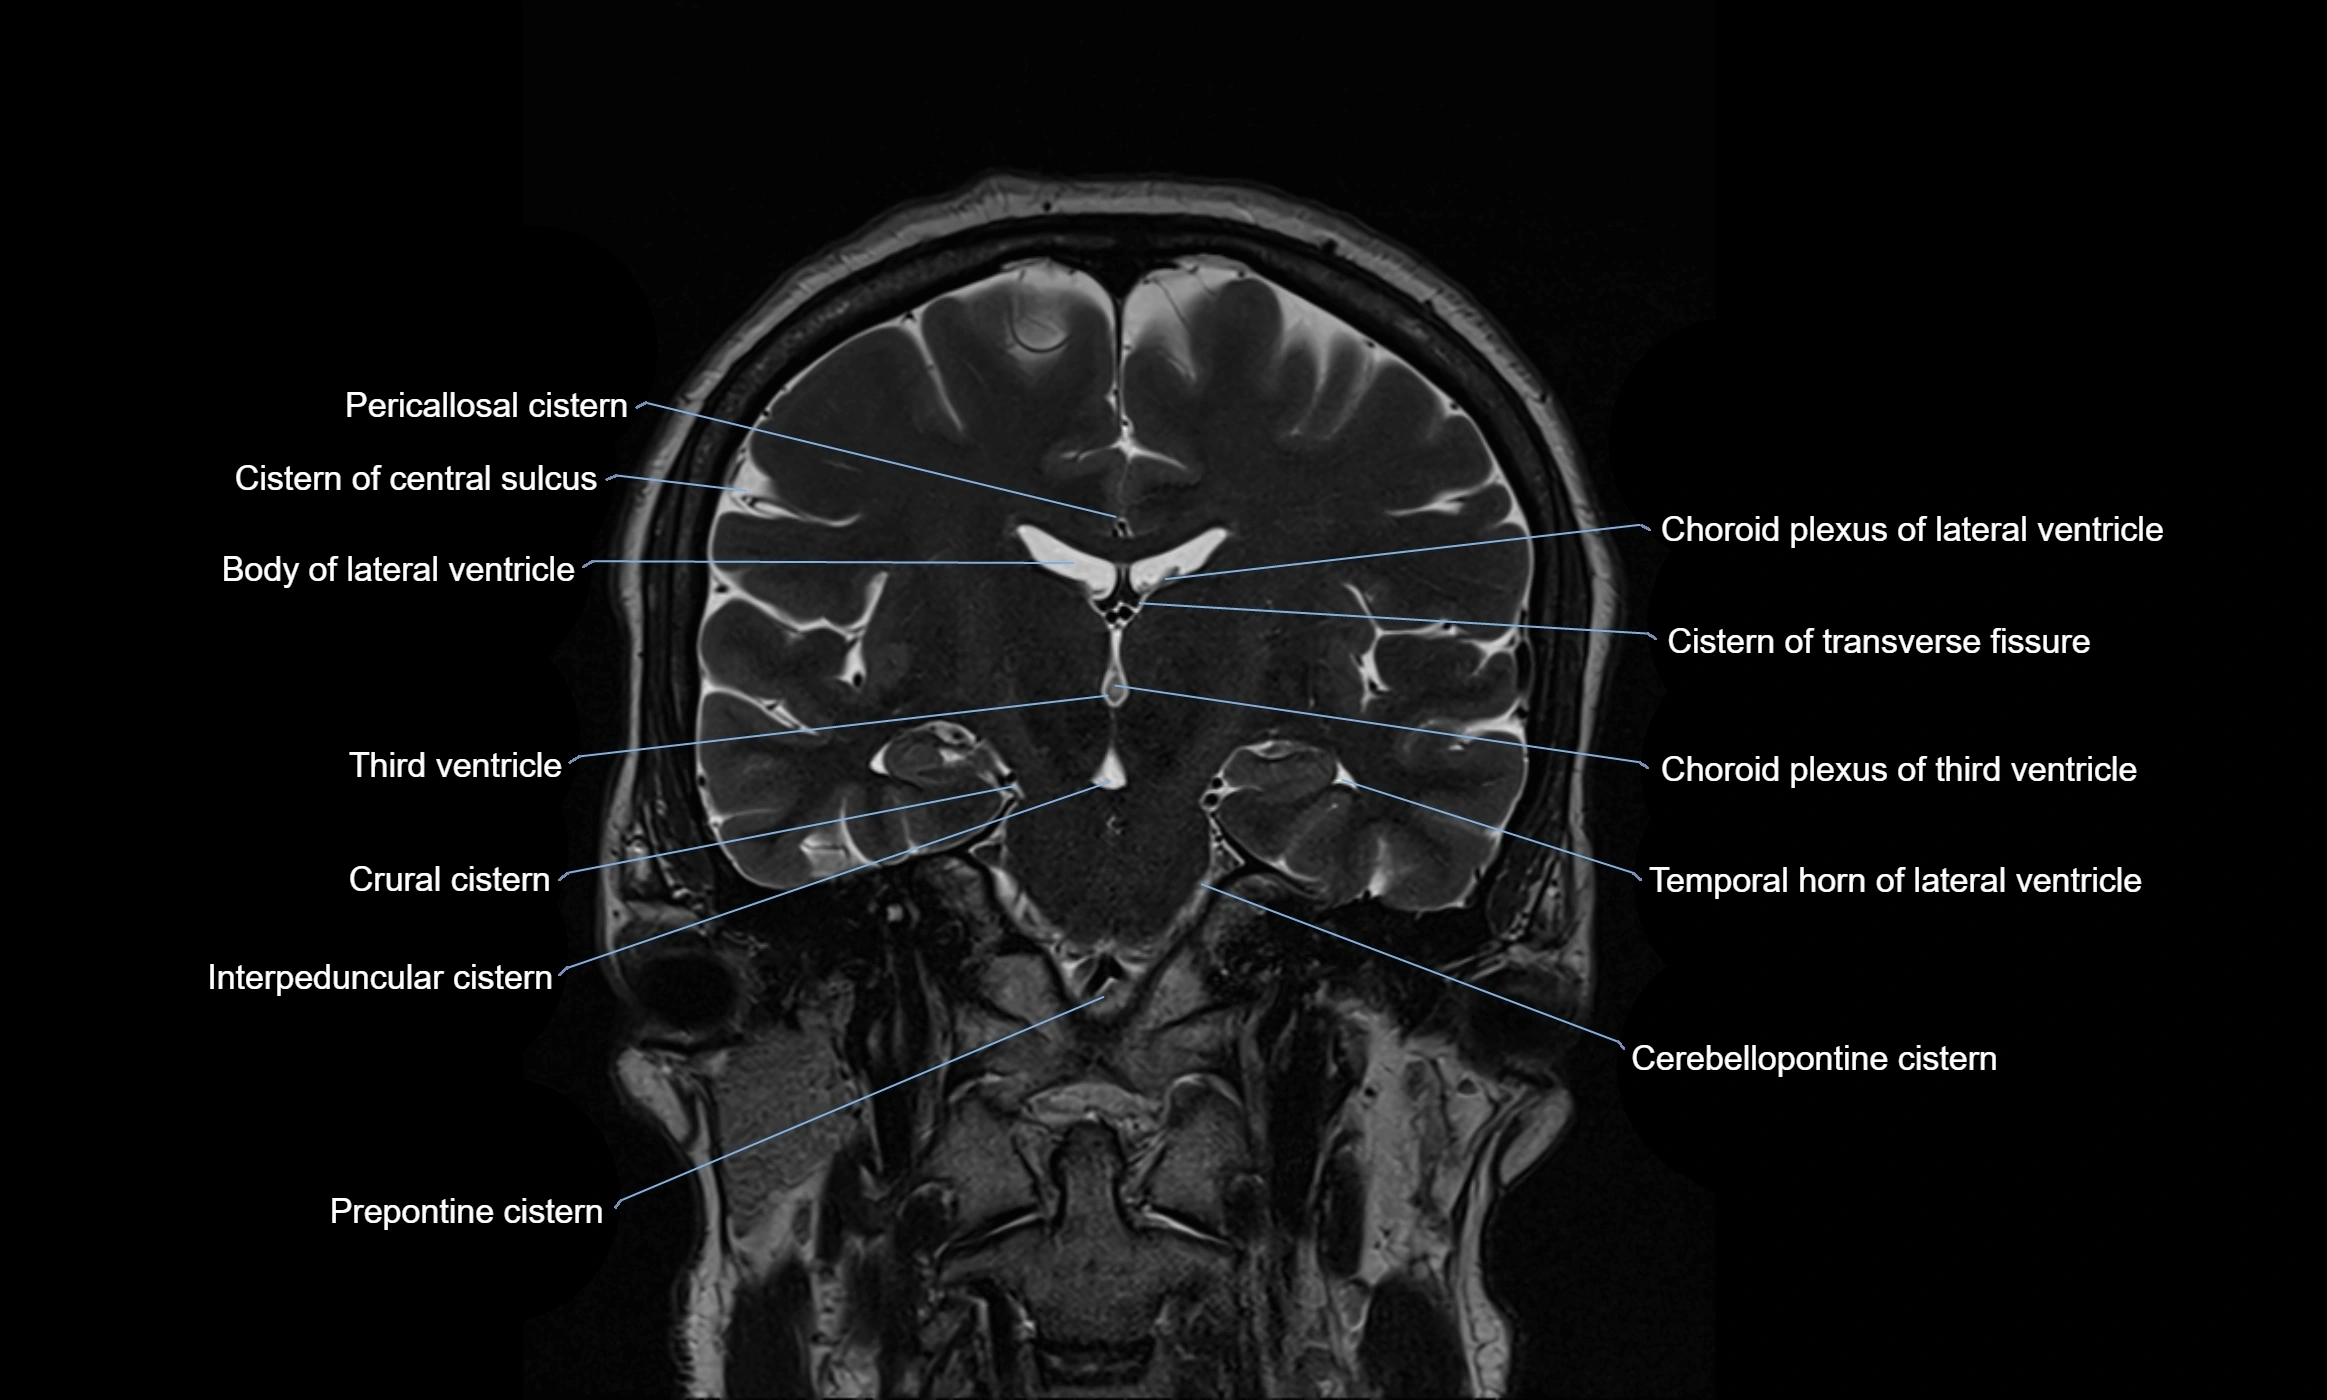

MRI images

image